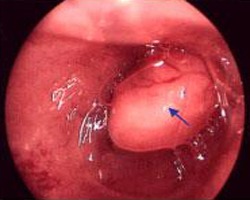

Грануляционный полип – это опухолевидное образование, возникающее в результате избыточного роста грануляционной ткани. Он может образовываться на месте поврежденной ткани после хирургического вмешательства или в результате травмы. Такой полип может иметь как узкое, так и широкое основание.

Основным методом лечения полипоза является гистероскопия – это хирургическая процедура, направленная на удаление новообразований. В ходе операции используется специальный инструмент – гистероскоп, который вводится в полость матки. Во время процедуры врач исследует внутренние органы и удаляет полипы. Извлеченные образования отправляются на гистологическое исследование для определения их структуры и проверки на наличие атипичных клеток.